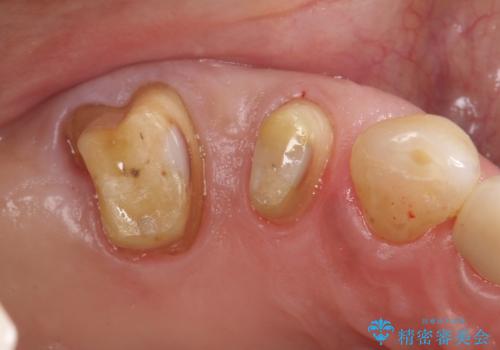

歯周病の進行した歯の抜歯。オールセラミッククラウン

- 以前に他院にて治療した歯が痛いことを主訴に来院されました。

最後方臼歯は根尖部まで歯周病が進行しており、抜歯を行なったのち、残存歯は歯周外科を行なったのちオールセラミッククラウンにて修復治療を行なっています。